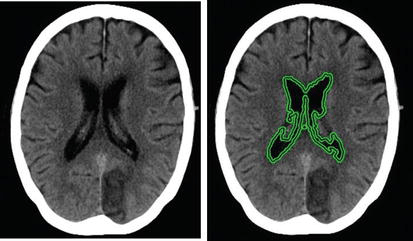

Pengolahan citra medis telah menjadi bidang yang semakin penting dalam dunia kedokteran modern. Salah satu teknik yang digunakan dalam pengolahan citra medis adalah segmentasi, yaitu proses pemisahan objek atau struktur yang ingin diidentifikasi dari latar belakang citra. Dalam kasus citra kepala MRI (Magnetic Resonance Imaging), segmentasi dapat membantu dokter dalam mendiagnosis dan memahami kondisi pasien dengan lebih baik. Salah satu metode yang digunakan dalam segmentasi citra kepala MRI adalah metode Active Contour.

Citra kepala MRI menyediakan informasi rinci tentang struktur otak, jaringan lunak, dan abnormalitas potensial lainnya dalam area kepala. Namun, citra-citra ini sering kali penuh dengan noise dan memiliki kontras yang bervariasi, membuat tugas segmentasi menjadi tantangan yang kompleks. Metode Active Contour, juga dikenal sebagai “Snake” atau “Level Set”, adalah salah satu metode yang membantu mengatasi tantangan ini.

Segmentasi citra kepala MRI menggunakan metode Active Contour adalah teknik yang bermanfaat dalam bidang kedokteran di mana ketelitian dan akurasi sangat penting. Dengan kemampuannya untuk menyesuaikan diri dengan batas objek yang rumit dan beragam, metode ini membantu dokter dalam menganalisis citra kepala MRI dengan lebih baik, mendukung diagnosis yang lebih tepat, dan memfasilitasi perencanaan pengobatan yang lebih efektif. Meskipun memiliki beberapa tantangan, metode Active Contour tetap menjadi pilihan yang kuat dalam pengolahan citra medis.

Contoh penerapan segmentasi citra kepala MRI menggunakan metode active contour dapat dilihat pada video berikut ini: